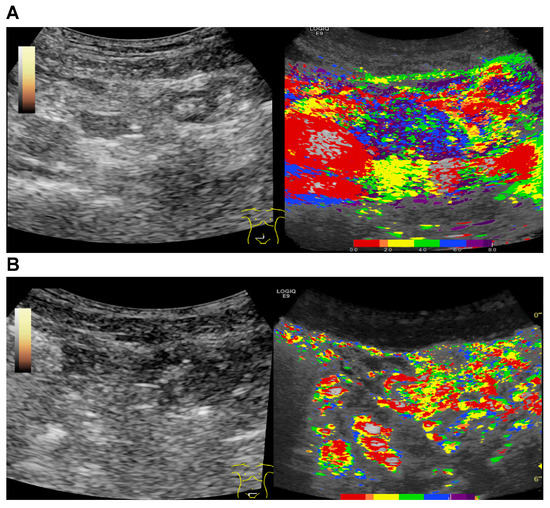

2.4. CEUS

2.5. Parametric Analysis